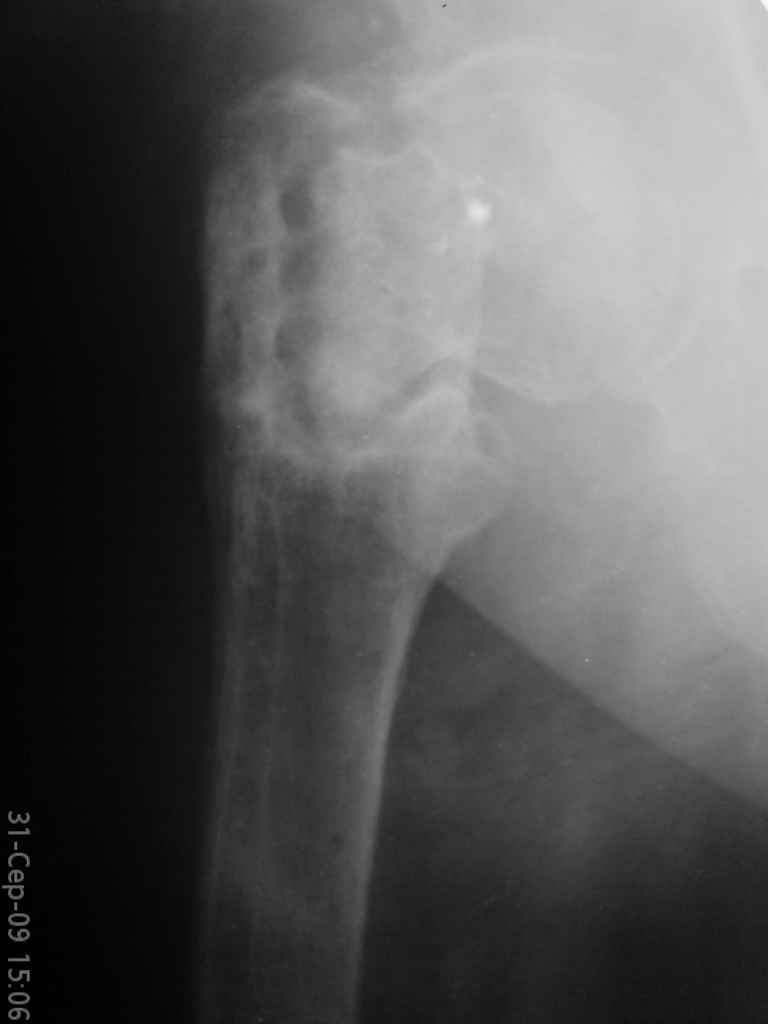

Уважаемые коллеги, помогите определиться с тактикой лечения. Больная, 62 года,жалуется на боли,неопорность левой ноги. Ходит с помощью костылей, укорочение ноги 3 см. Два года назад была оперирована кокой-то накостной пластиной, пластину удалили 4 мес назад. Вопрос такой: предлагать эндопротезирование или делать МОС (что-то по типу стержня Gamma)?За качество снимков извините, по данным МРТ - головка живая

>по данным МРТ - головка живая

Исследования показывают, что даже при частичном остеонекрозе головки бедра вальгусная остеотомия положительно влияет на восстановление кровообращения.

Секрет успеха в более благоприятной механике, за счет установки линии перелома в более горизонтальное положение. Вальгусная остеотомия создает необходимые механические условия для сращения ложного сустава в шейке и в вертельной области, а также восстанавливает длину конечности. Но любая вальгизирующая операция приведет к неизбежному вальгусу конечности.

Для профилактики вальгуса конечности необходимо создать латерализазацию диафиза, и для быстрейшего сращения необходимо создать компрессию по линии остеотомии.

Интрамедуллярной конструкцией трудно создать все эти условия и поэтому для окончательной фиксации применение 120 или 130 градусной пластины считаю более привлекательным вариантом.